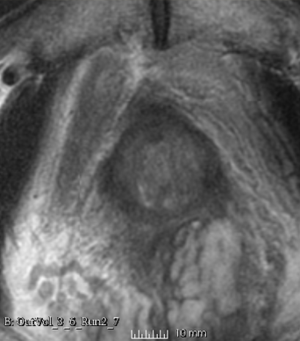

Case 8

Reference intraop volume

Reg Result Slicer 3.6 with ITKv3

Reg Result Slicer 4.4 with ITKv4